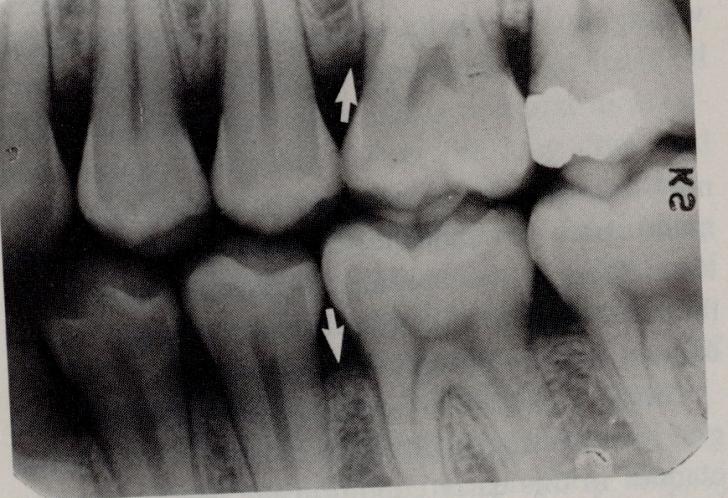

PARODONTITE MARGINALE CRONICE

PARODONTITE MARGINALE CRONICE Prepubertara 1-12 ani Juvenila 13-20 ani Rapid progresiva A adultului >30 ani n ½ din populatia adulta n Citeste tot ... 936 cuvinte

Dimensiune mica

+ cu imagini |